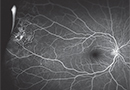

HORV: A Rare But Devastating Complication of Endophthalmitis Prophylaxis

Hemorrhagic occlusive retinal vasculitis has been associated with routine intracameral vancomycin use.